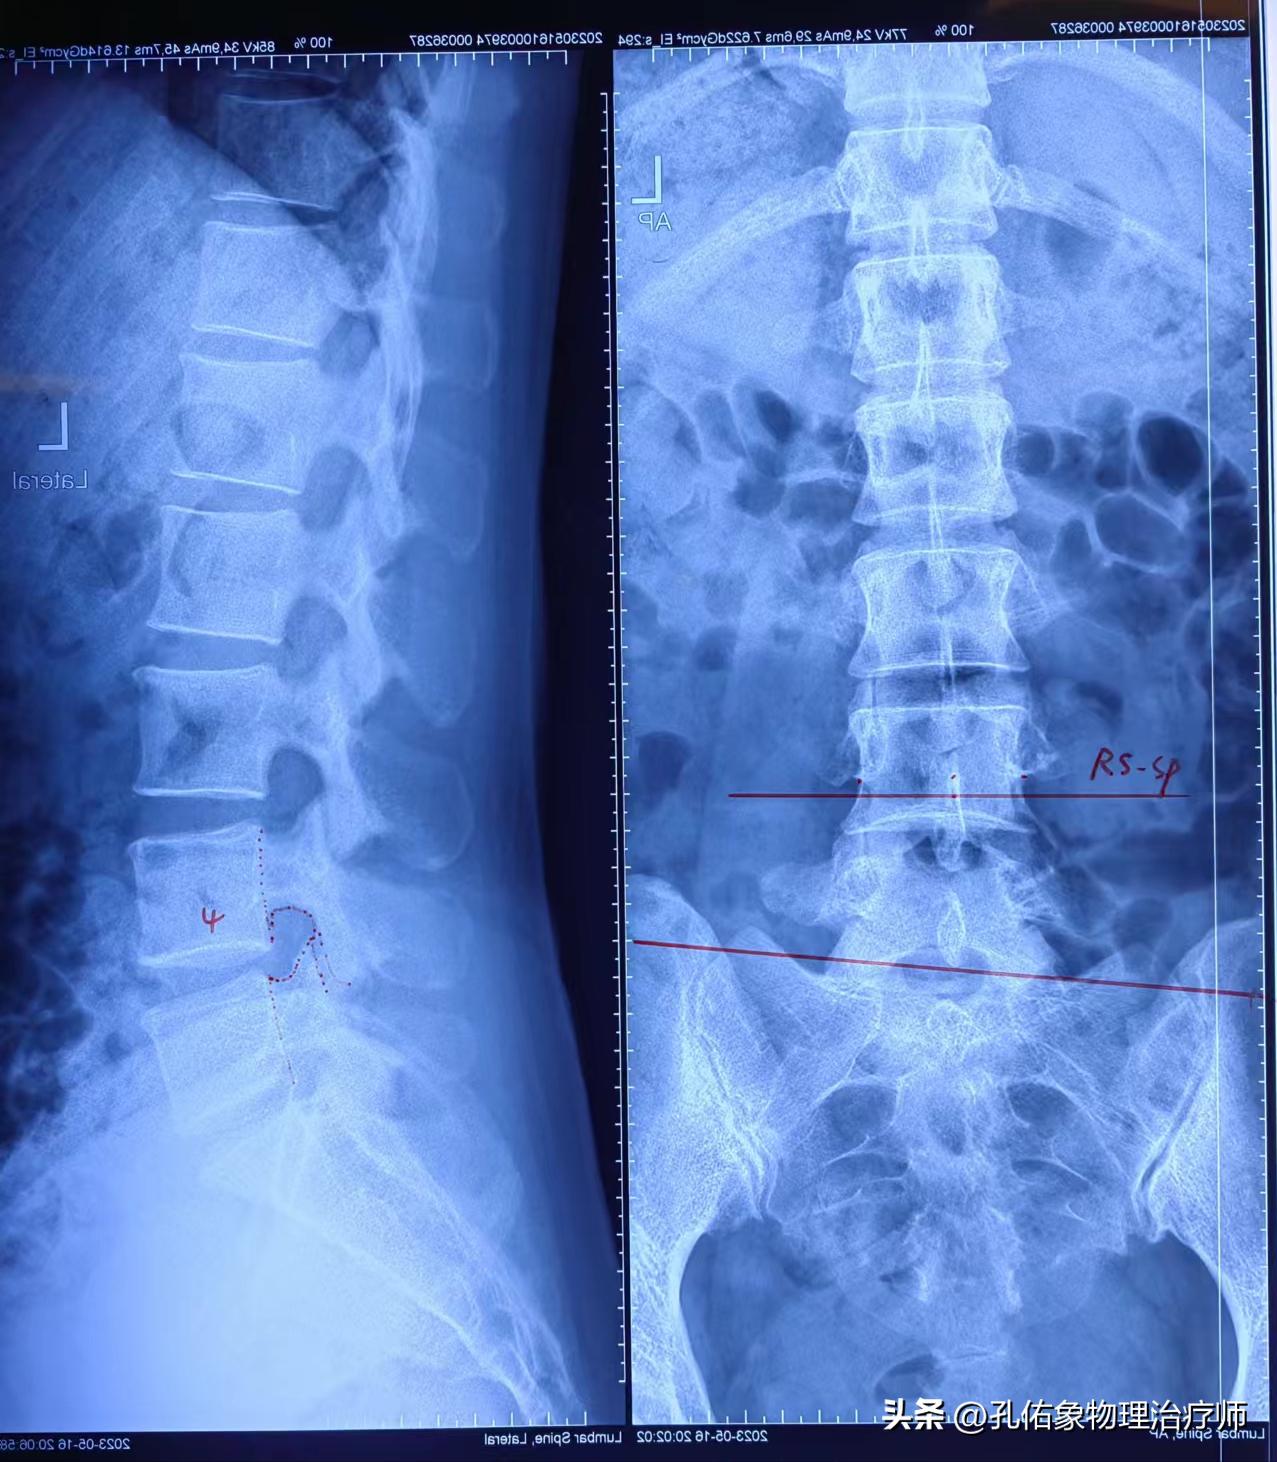

让其拍摄腰部X片,结果如下图所示:

阅片得知,腰4椎体相对腰5椎体后下移位,并发生旋转;脊柱向左侧侧弯,左右骨盆不对称,左侧骶髂关节钙化。